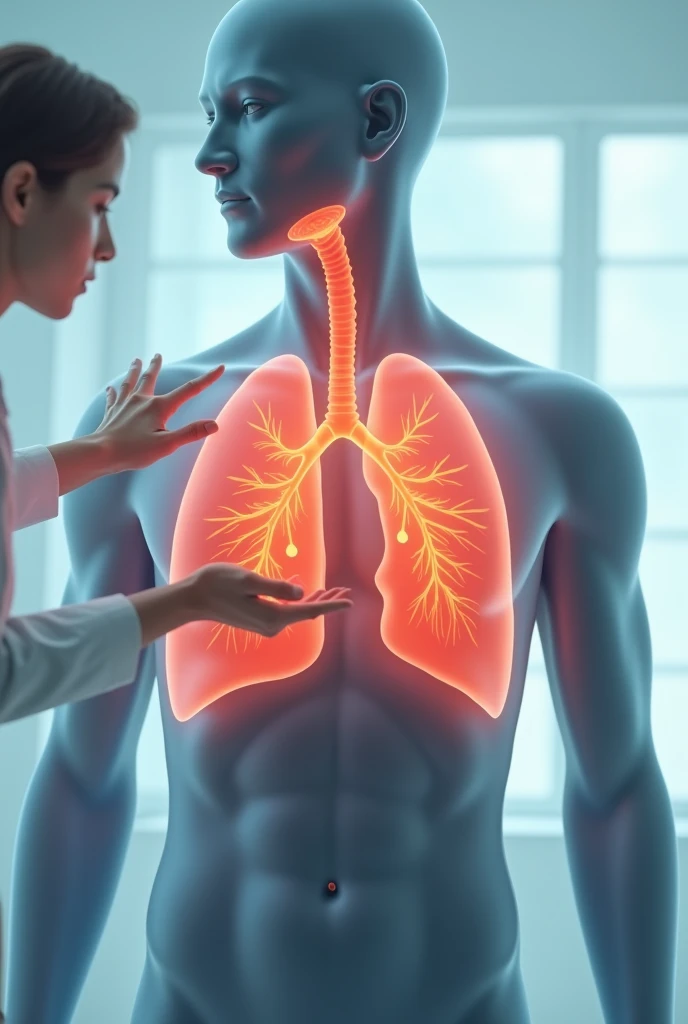

Make a folder about bacterial pneumonia

Make a folder about bacterial pneumonia

Make a folder about bacterial pneumonia